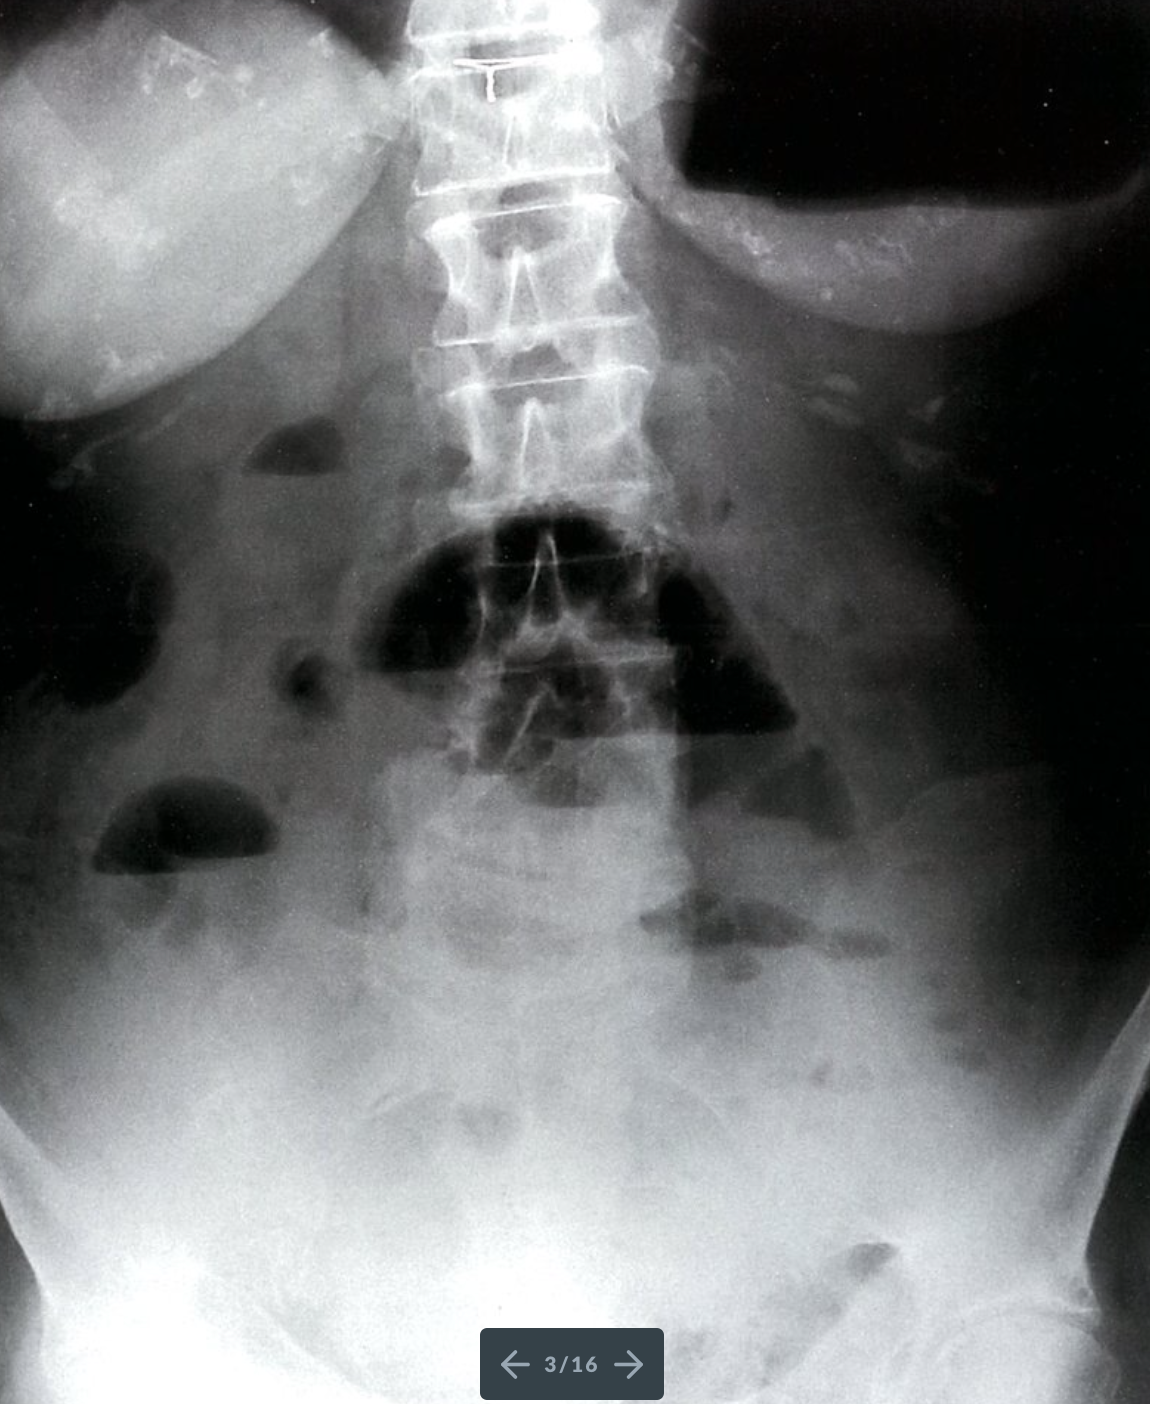

Mechanical small bowel obstruction

X-ray abdomen (AP view; erect position)

Multiple air-fluid levels (green overlay) are visible in the mid-abdomen. The opaque appearance of the pelvis (red overlay) is due to fluid-filled loops of small bowel. There is a paucity of gas in the colon, and an air-fluid level is present in the dilated stomach (S).

Erect and decubitus radiographs can reveal air-fluid levels that are not identifiable on supine radiographs. Air-fluid levels can indicate ileus or mechanical obstruction. A lack of distal gas and air-fluid levels at different heights in the same bowel loop (differential air-fluid levels) suggest obstruction